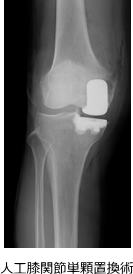

- 単顆置換術(UKA):内側または外側の限局した変形に対して、痛んだ側のみを置換